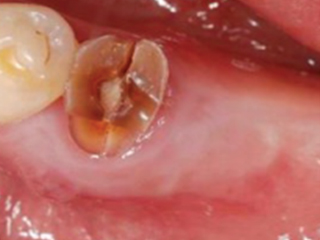

신경치료 중 치료는 마지막까지 하지 않고 방치하게 되면 치아는 신경이 없는 상태로 방치되는 것이기 때문에 까맣게 변색이 됩니다.

치아가 녹아버리거나 부러져버리는 상황에 이르게 됩니다.

신경치료를 위해 치아가 아래ㆍ위 치아가 닿지 않게 조절을 하며 치아에 구멍을 뚫어 놓기 때문에

씌워야 기능을 수복할 수 있습니다.